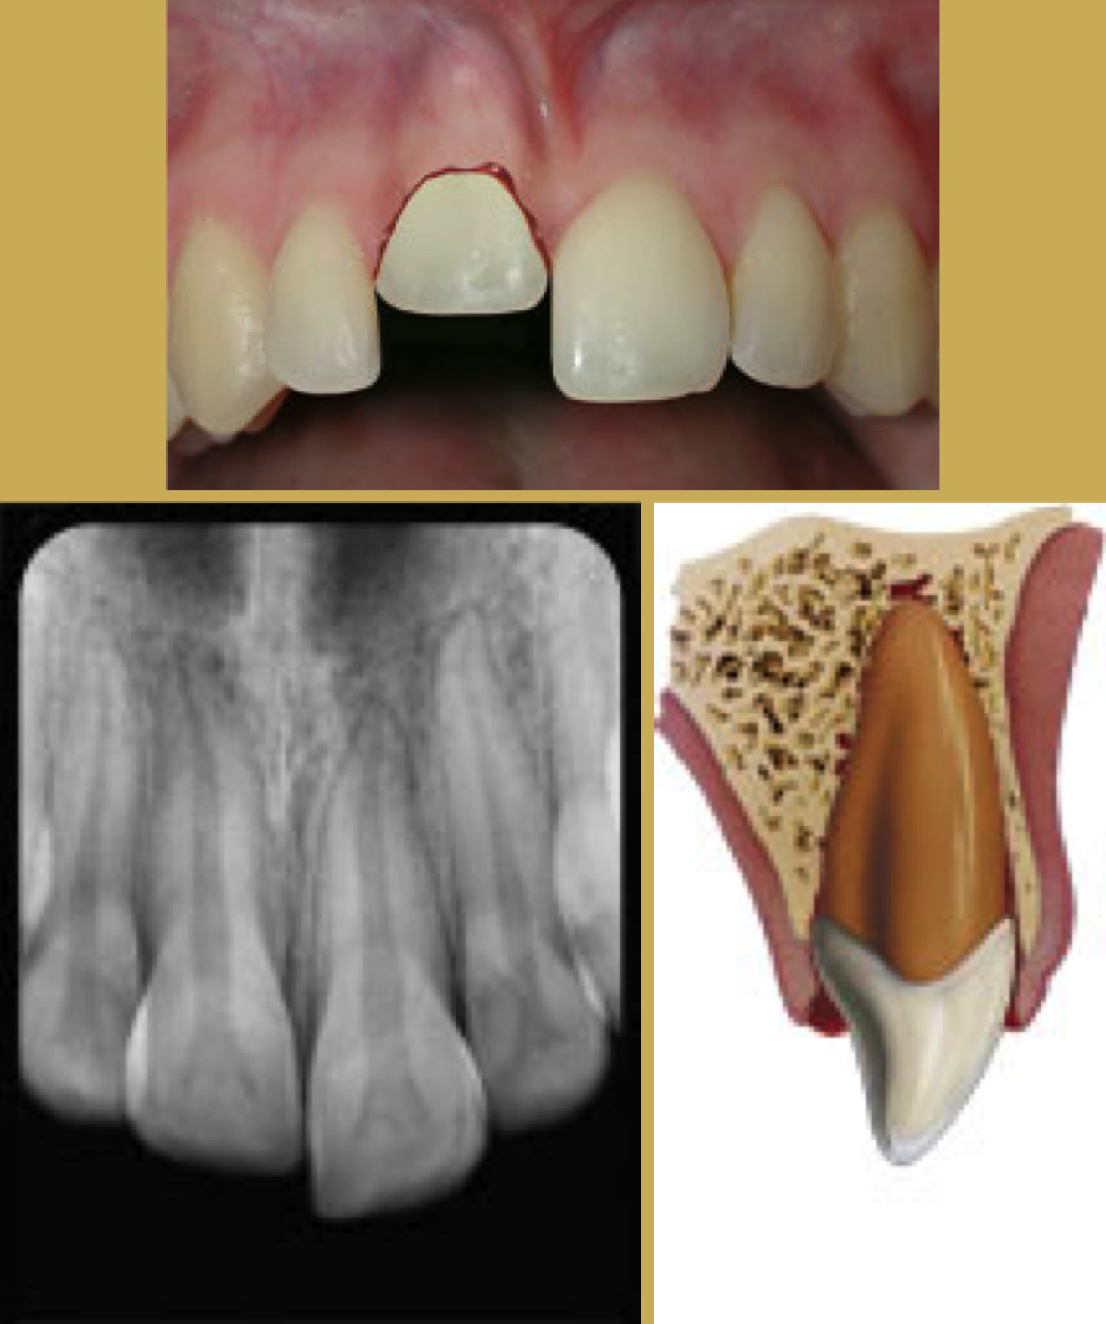

Tooth Intrusion

Tooth intrusion occurs when the tooth has been driven into the alveolar process due to an axially directed impact (Figure 3). This is the most severe form of displacement injury. Athletes with intrusively luxated teeth should be immediately removed from play and transported to a sports emergency dentist.44

Pulpal necrosis occurs in 96% of intrusive displacements and is more likely to occur in teeth with fully formed roots. Immature root development will usually mean spontaneous re-eruption. Mature root development will require repositioning, surgery, and splinting or orthodontic extrusion. Treat relatively quickly since the pulp usually becomes necrotic - this can be treated with temporary filling of calcium hydroxide paste followed by root canal therapy.

Fig 3. Images of Intrusion

Figure 3